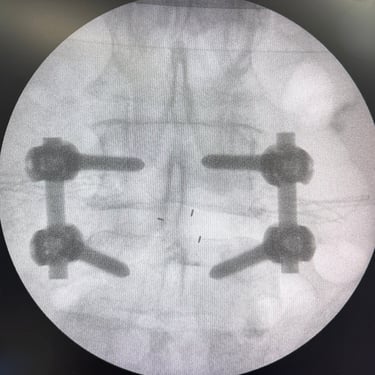

Estabilización con Fijación Transpedicular (FTP) y Fusión Intersomática Transforaminal (TLIF)

La listesis L4–L5 asociada a estenosis lumbar severa se caracteriza por el deslizamiento vertebral y el estrechamiento del canal espinal, generando dolor lumbar, claudicación neurogénica y compromiso radicular. Cuando el tratamiento conservador no logra un control adecuado de los síntomas, la fijación transpedicular (FTP) asociada a la fusión intersomática transforaminal (TLIF) constituye una alternativa quirúrgica eficaz. Este procedimiento permite descomprimir las estructuras nerviosas, restaurar la alineación vertebral y proporcionar una estabilización sólida del segmento afectado, favoreciendo una recuperación funcional segura y una mejor calidad de vida.